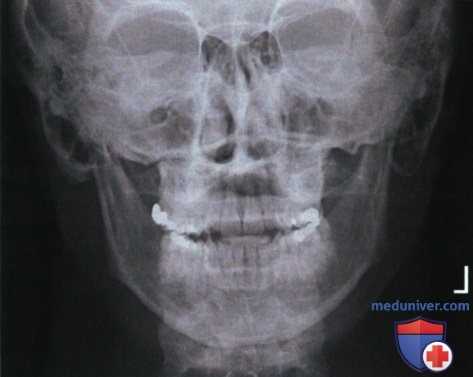

Рекомендации по анализу рентгенограммы черепа и нижней челюсти в ЗП или ПЗ проекции

Рекомендации по анализу качества рентгенограмм (рис. 1 и 2):

РИСУНОК 1 Рентгенограммы черепа в ЗП и ПЗ проекциях, правильное расположение. РИСУНОК 2 Рентгенограмма нижней челюсти в ЗП проекции, правильное расположение.

• Череп: расстояние между латеральным краем глазницы и латеральным краем черепа с обеих сторон одинаково (рис. 4)

• Нижняя челюсть: расстояние между ветвью нижней челюсти и латеральным краем шейных позвонков с обеих сторон одинаково, ветви нижней челюсти имеют одинаковую ширину (рис. 5)

• Череп: передние наклоненные отростки тела клиновидной кости и спинка турецкого седла визуализируются выше пазух решетчатой кости; каменистые гребни и надглазничные края накладываются друг на друга; внутренний слуховой проход направлен горизонтально и виден в центре глазницы (рис. 6 и 7)

• Нижняя челюсть: отростки мыщелков нижней челюсти визуализируются сквозь сосцевидные отростки; отсутствует проекционное укорочение ветвей нижней челюсти (рис. 8 и 9)

• Нижняя челюсть: челюсти сжаты.

• Костная перегородка носа располагается по длинной оси экспозиционного поля

• Череп: надглазничные края находятся на одном горизонтальном уровне (рис. 14)

• Нижняя челюсть: ВНС видны на одном горизонтальном уровне

• Череп: спинка турецкого седла находится в центре экспозиционного поля

• Нижняя челюсть: середина отрезка между ветвями нижней челюсти находится в центре экспозиционного поля

• Череп: в экспозиционное поле входят наружный контур свода черепа и верхнечелюстные пазухи.

• Нижняя челюсть: в экспозиционное поле входит вся нижняя челюсть

РИСУНОК 3 Правильное положение пациента для рентгенографии черепа в ЗП проекции. РИСУНОК 4 Рентгенограмма черепа в ЗП проекции. Голова была повернута лицом влево. РИСУНОК 5 Рентгенограмма нижней челюсти в ЗП проекции. Голова была повернута лицом вправо. РИСУНОК 6 Рентгенограмма черепа в ЗП проекции. Подбородок был опущен недостаточно, чтобы расположить ОМЛ перпендикулярно ПИ. РИСУНОК 7 Рентгенограмма черепа в ЗП проекции. Подбородок был опущен избыточно, чтобы расположить ОМЛ перпендикулярно ПИ.